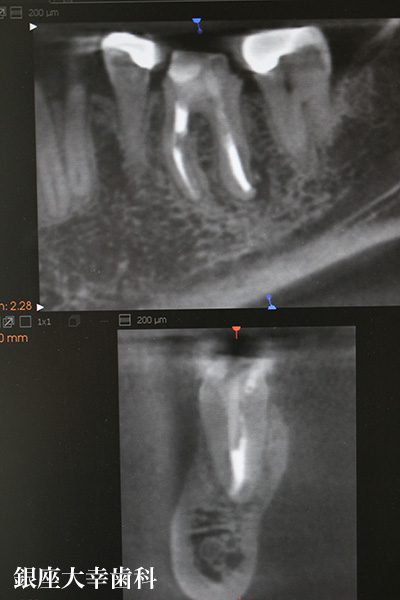

この患者さんは他医院で根管治療したが痛みが取れなくて来院した 患者さんです。

術前のCTを見ても決して根管治療が不完全な訳ではありませんで した。

↑術前のCT

↑MTA剤を含んだシーラーを使い根管充填

根管治療は徹底的に異物を除去し、FCを中和することにしました。 術後1ヶ月でMTA剤を含んだシーラーを使い根管充填をしました。 この時点でも根尖には4.5㎜×7.7㎜の病巣が確認できます。

↑術後6ヶ月のCT写真

根管充填後、咬合痛や違和感がありましたが、この時点では問題ありませんでした。 現時点でも仮歯で経過を観察していますが、根尖にあった骨の透過像(根尖病巣)は縮小していました。 組織再生能があるMAT剤がセメント質を再生し、セメント質が骨の再生を誘導したものだと考えられます。